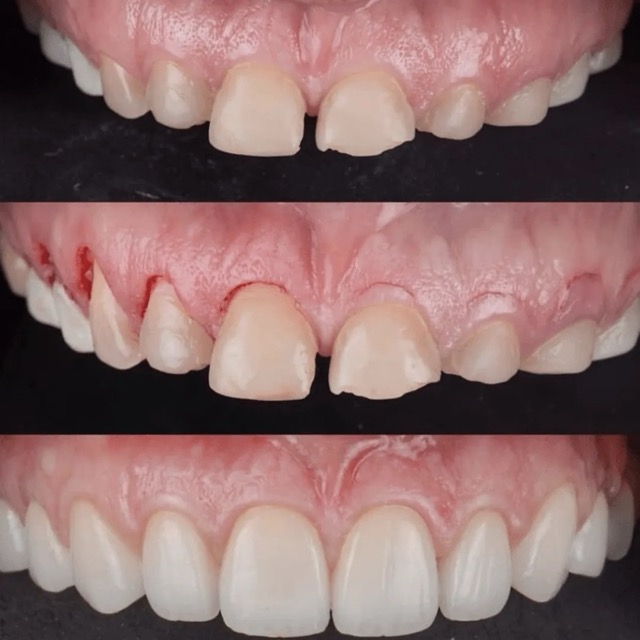

Patient presented to the office with a concern that the teeth were small and that too much gum shows when smiling. A comprehensive exam with x rays, pictures, smile analysis was done.

After understanding the expectations it was decided that the patient needed gum contouring to lift the gums to give bigger teeth to compliment facial anatomy. Temporary veneers were fabricated that were tested by the patient for a week to determine if patient was comfortable with the bite and the way the veneers looked. Finally the hand crafted veneers were fabricated by the lab and meticulously cemented by the doctor to achieve the contour and anatomy that was decided in the beginning of the appointment.